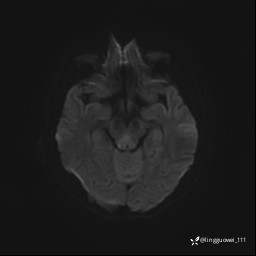

DWI ADC

img